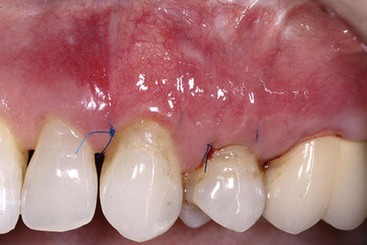

image

Supplement A Figure 63-5 Pouch coronally positioned and sutured.